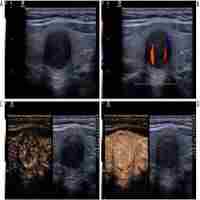

| Abstract | Background: The role of next generation sequencing (NGS) for identifying high risk mutations in thyroid nodules following fine needle aspiration (FNA) biopsy continues to grow. However, ultrasound diagnosis even using the American College of Radiology’s Thyroid Imaging Reporting and Data System (TI-RADS) has limited ability to stratify genetic risk. The purpose of this study was to incorporate an artificial intelligence (AI) algorithm of thyroid ultrasound with object detection within the TI-RADS scoring system to improve prediction of genetic risk in these nodules. Methods: 252 nodules from 249 patients that underwent ultrasound imaging and ultrasound-guided FNA with NGS with or without resection were retrospectively selected for this study. A machine learning program (Google AutoML) was employed for both automated nodule identification and risk stratification. 201 nodules were used for model training and 51 reserved for testing. Three blinded radiologists scored the images of the test set nodules using TI-RADS and assigned each nodule as high or low risk based on the presence of highly suspicious imaging features on TI-RADS (very hypoechoic, taller-than-wide, extra-thyroidal extension, punctate echogenic foci). Subsequently, the TI-RADS classification was modified to incorporate AI for T4 nodules while treating T1-3 as low risk and T5 as high risk. All diagnostic predictions were compared to the presence of a high-risk mutation and pathology when available. Results: The AI algorithm correctly located all nodules in the test dataset (100% object detection). The model predicted the malignancy risk with a sensitivity of 73.9%, specificity of 70.8%, positive predictive value (PPV) of 70.8%, negative predictive value (NPV) of 73.9% and accuracy of 66.772.4% during the testing. The radiologists performed with a sensitivity of 52.1±4.4%, specificity of 65.2±6.4%, PPV of 59.1±3.5%, NPV of 58.7±1.8%, and accuracy of 58.8±2.5% when using TI-RADS and sensitivity of 53.6±17.6% (p=0.87), specificity of 83.3±7.2% (p=0.06), PPV of 75.7±8.5% (p=0.13), NPV of 66.0±8.8% (p=0.31), and accuracy of 68.7±7.4% (p=0.21) when using AI-modified TI-RADS. Conclusions: Incorporation of AI into TI-RADS improved radiologist performance and showed better malignancy risk prediction than AI alone when classifying thyroid nodules. Employing AI in existing thyroid nodule classification systems may help more accurately identifying high-risk nodules. |